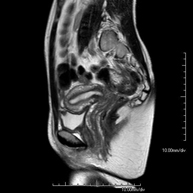

Prova diagnòstica no invasiva que consisteix en l'obtenció d'imatges d'alta definició anatòmica de l'abdomen mitjançant l'ús d'un camp electromagnètic i ones de ràdio (amb un emissor i un receptor). No utilitza radiació ionitzant. En aquesta exploració s'inclouen el fetge, el pàncrees, la melsa, la via biliar, la vesícula biliar, les glàndules suprarenals, els ronyons, l'aorta abdominal, la vena cava inferior, l'estómac, el duodè, etc. En alguns casos caldrà emprar contrast paramagnètic (Gadolini) per caracteritzar les lesions. - RM Pelvis femenina

Prova diagnòstica no invasiva que consisteix en l'obtenció d'imatges d'alta definició anatòmica de la pelvis mitjançant l'ús d'un camp electromagnètic i ones de ràdio (amb un emissor i un receptor). No utilitza radiació ionitzant. Es realitza per a l'estudi de patologies d'úter, d'ovari, de trompes i de vagina, ja siguin d'origen tumoral, inflamatori o vascular. També permet valorar les estructures adjacents localitzades a la pelvis i la identificació de les seves alteracions. De vegades és necessari l'ús de contrast intravenós (Gadolini) per caracteritzar les lesions. - RM Pelvis masculina